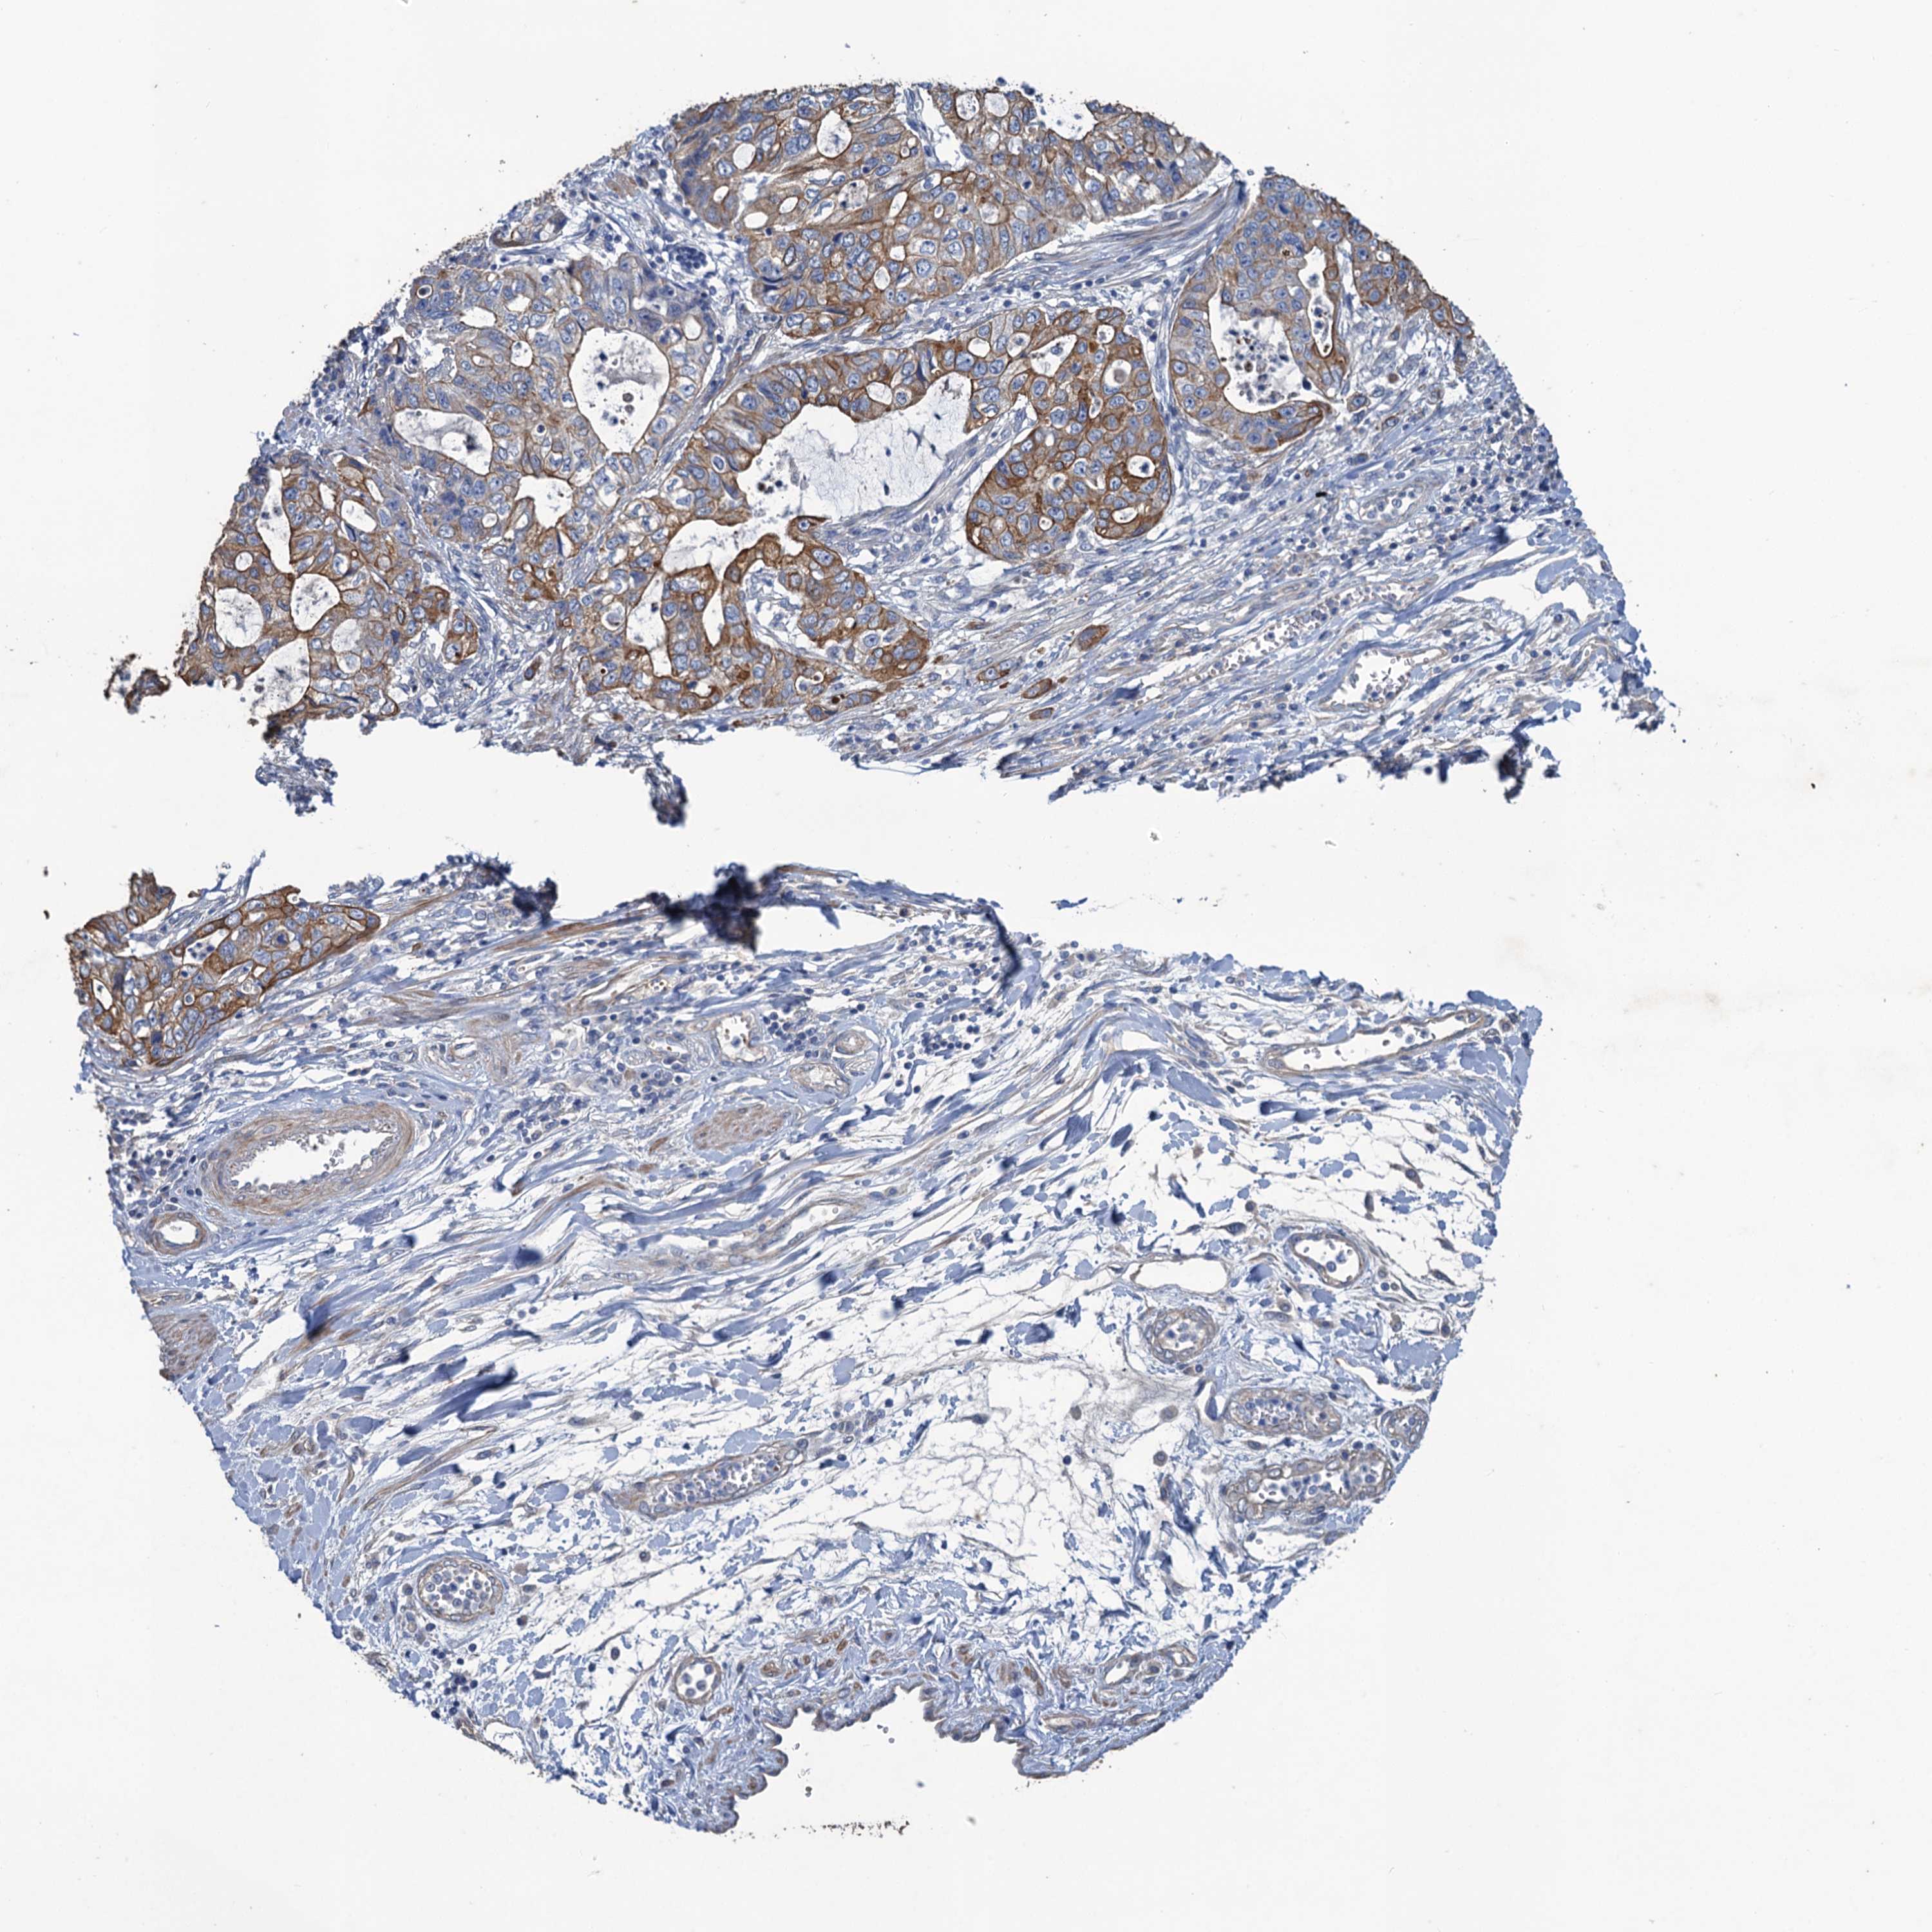

STOMACH CANCER - Protein expressioni

A mouse-over function shows sample information and annotation data. Click on an image to view it in a full screen mode. Samples can be filtered based on level of antibody staining by selecting one or several of the following categories: high, medium, low and not detected. The assay and annotation is described here.

Note that samples used for immunohistochemistry by the Human Protein Atlas do not correspond to samples in the TCGA dataset.

Antibody stainingi

Antibody staining in the annotated cell types in the current human tissue is reported as not detected, low, medium, or high, based on conventional immunohistochemistry profiling in selected tissues. This score is based on the combination of the staining intensity and fraction of stained cells.

Each image is clickable and will lead to virtual microscopy that enables deeper exploration of all samples and also displays staining intensity scores, fraction scores and subcellular localization as well as patient and tissue information for each sample.

Antibody HPA040574

Antibody HPA047804

Staining

High

Medium

Low

Not detected

Intensity

Strong

Moderate

Weak

Negative

Quantity

>75%

75%-25%

<25%

None

Location

Nuclear

Cytoplasmic/membranous

Cytoplasmic/membranous,nuclear

Adenocarcinoma, NOS

Adenocarcinoma, High grade